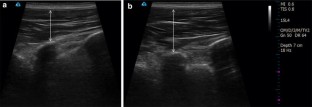

Chronic low back pain (CLBP) is often associated with impaired control of deep trunk muscles and reorganization of the primary motor areas (M1). Precisely, functional changes of the lumbar multifidus muscles (MF) involved in spine stability may be of special interest in rehabilitation. Therefore, we tested MF corticomotor control using double transcranial magnetic stimulation (TMS) paradigms for the first time in this muscle and examined its link with MF volitional activation. Eleven individuals with lateralized CLBP and 13 pain-free participants were recruited. Ultrasound imaging enabled measurement of MF volitional isometric contraction in prone lying. TMS of MF M1 area was used to test hemispheric excitability and mechanisms in relation to motor programming, i.e., active motor threshold (AMT), amplitude of motor-evoked potentials and short-interval intracortical inhibition (SICI) and facilitation (SICF). In CLBP, SICI level was lower in the left hemisphere and MF volitional contraction was not related to AMT (M1 excitability), conversely to what was observed in the pain-free group. No other between-group difference was detected. These original findings support a plasticity of cortical maps controlling paravertebral muscles and likely including a different motor strategy for the control of MF. Changes of M1 function may thus underlie impaired motor control of lumbopelvic spine and pain persistence in CLBP.

Kiesel KB, Uhl TL, Underwood FB, Rodd DW, Nitz AJ (2007a) Measurement of lumbar multifidus muscle contraction with rehabilitative ultrasound imaging. Man Ther 12:161–166. doi:10.1016/j.math.2006.06.011

Van K, Hides JA, Richardson CA (2006) The use of real-time ultrasound imaging for biofeedback of lumbar multifidus muscle contraction in healthy subjects. J Orthop Sports Phys Ther 36:920–925

Wallwork TL, Hides JA, Stanton WR (2007) Intrarater and interrater reliability of assessment of lumbar multifidus muscle thickness using rehabilitative ultrasound imaging. J Orthop Sports Phys Ther 37:608–612

Wallwork TL, Stanton WR, Freke M, Hides JA (2009) The effect of chronic low back pain on size and contraction of the lumbar multifidus muscle. Man Ther 14:496–500. doi:10.1016/j.math.2008.09.006